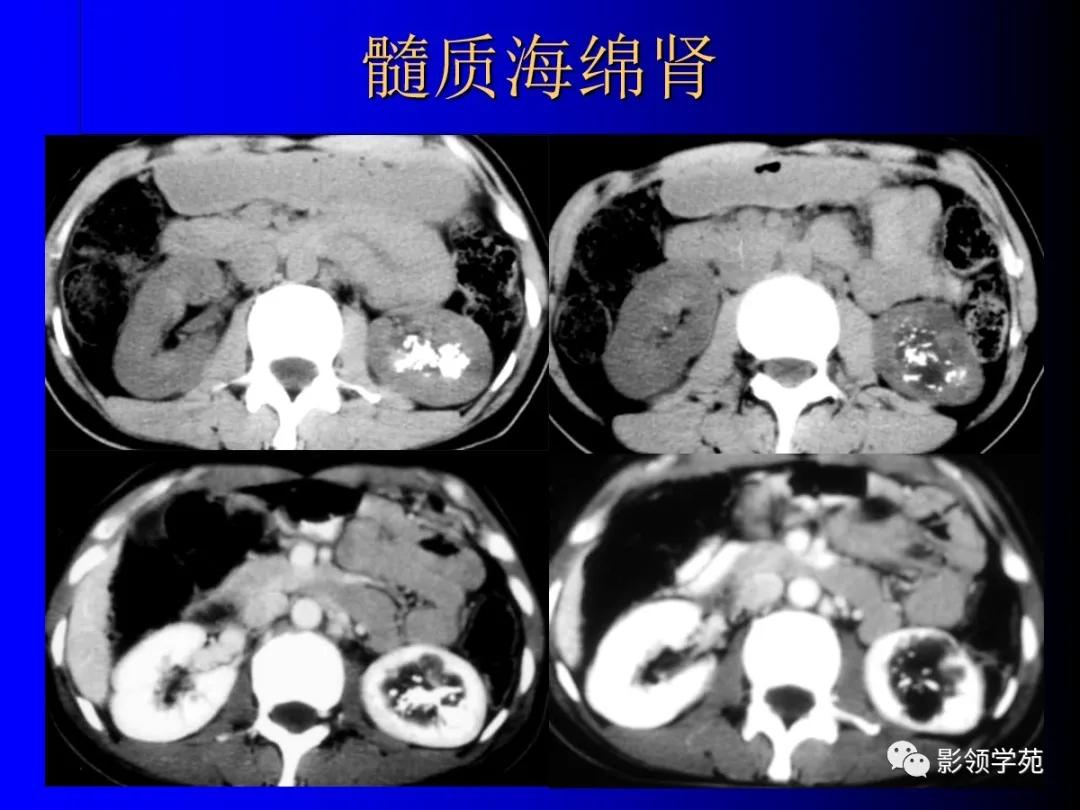

7、髓质海绵肾(Medullary Sponge Kidney )

非遗传性的以肾集合管囊状扩张为特征的肾髓质发育异常。

-

常见于40-50岁患者,女多于男。

可无症状,易合并炎症和结石。临床上可出现肾绞痛,间隙性血尿和脓尿。